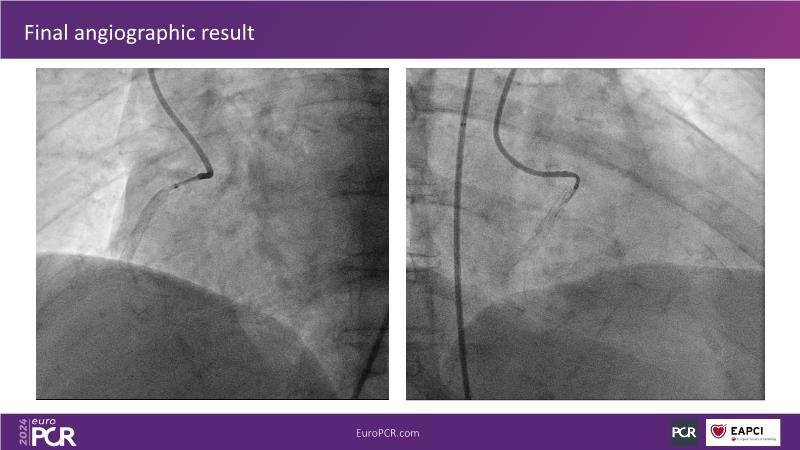

Follow this session to learn about the novel HC-IVL system, its application for moderate to severe calcified lesions, and procedural tips. The LithiX Hertz Contact IVL addresses unmet needs in coronary artery calcification by offering a simplified workflow with fewer devices and effective treatment for difficult lesions. Its novel design ensures safety and efficacy, with the PINNACLE I study's primary outcomes expected to confirm its effectiveness.